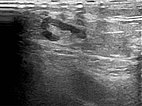

B-scan ultrasonography of the subcutaneous portion of the lymphatic malformation shows a dysplastic dilated lymphatic duct as an anechoic tubular structure. The surrounding subcutaneous adipose tissue is clearly more echogenic than normal due to the interspersed lymphatic fluid.

B-scan ultrasonography (cross-section of proximal ventral thigh) also shows the clearly echogenic tissue, interspersed with individual very fine, dilated, fluid-filled lymphatic ducts.